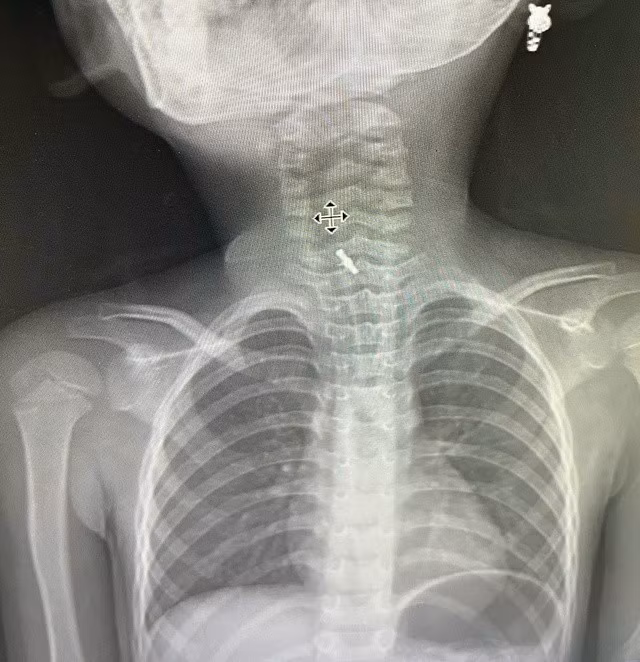

Hình ảnh chụp X-Quang xác định dị vật mắc tại thực quản. Ảnh BV